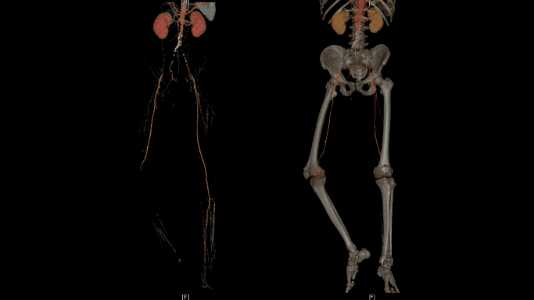

图2术前CT动脉重建,可见肾下主动脉、双侧髂动脉、右侧腘动脉闭塞